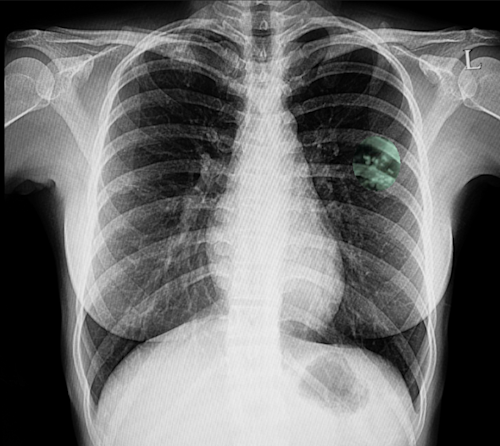

Above image shows calcified nodules in the left upper lobe, consistent with latent tuberculosis.